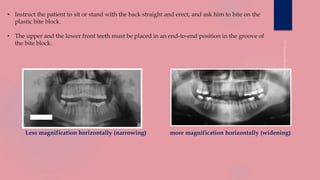

• Instruct the patient to sit or stand with the back straight and erect, and ask him to bite on the

plastic bite block.

• The upper and the lower front teeth must be placed in an end-to-end position in the groove of

the bite block.

Less magnification horizontally (narrowing) more magnification horizontally (widening)